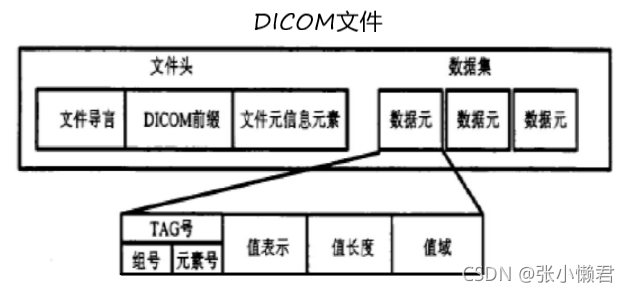

2、DICOM文件理解

DICOM文件包含一个头文件和一个数据集:

(1)文件头

128个字节的文件导言:用于应用简介和固定长度数据的详细说明。

4个字节的DICOM前缀:“DICM”,用于标识本文件是否是DICOM文件。

不定字节长度的文件元信息:包含文件元信息版本、媒体存储SOP类、传输语法、实现设备等。

(2)数据集

数据集是由若干个数据元组成,存储了病人和图像的相关信息。

数据元

一个数据元主要由标签(Tag),值类型(VR,Value Representation),数据值长度(Length),值域(VF,Value Field)几部分组成。

①标签Tag:4字节无符号整型,由组号和元素号组成,是数据元的唯一标识码,文件中Tag标签有大约2000个,我们只需要了解常用的Tag即可。